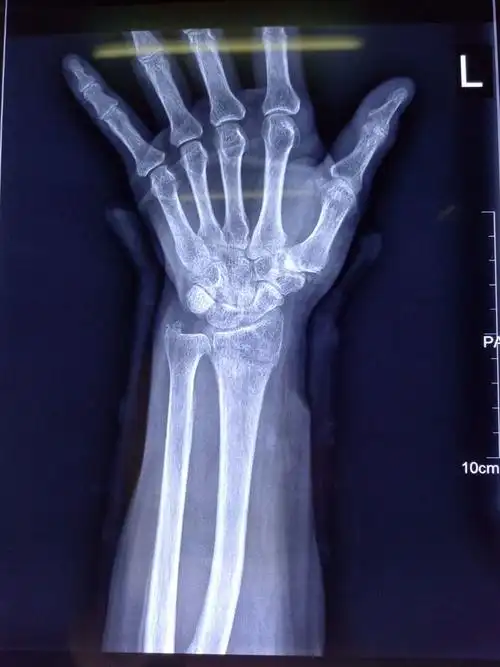

一文看懂桡骨远端骨折

桡骨远端骨折是怎么回事?好发于哪些人群?

13岁男孩,左桡骨远端骨骺骨折,予手法复位石膏固定,避免了手 - 抖音

晚间急诊-11岁小儿桡骨远端骨折骺滑脱,六七二骨科医院创伤骨 - 抖音

创伤日常手术之桡骨远端骨折

桡骨远端骨折手法复位一例